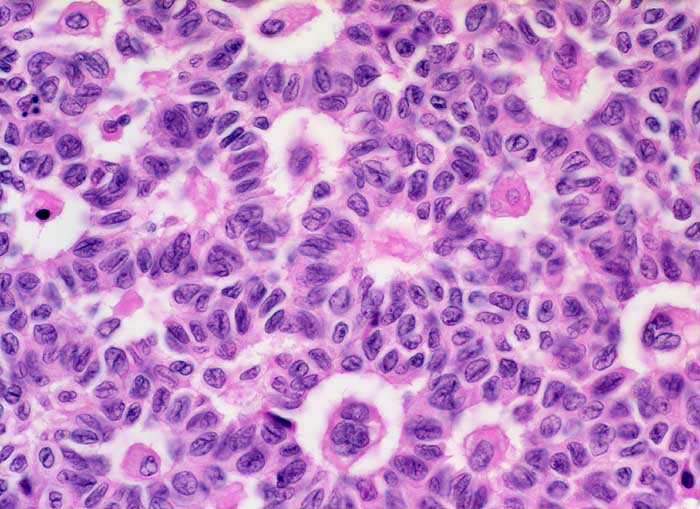

AP/ Granulosazelltumor des Ovars

Granulosazelltumor des Ovars

Ovar

Morphologie

Pathologischer Befund